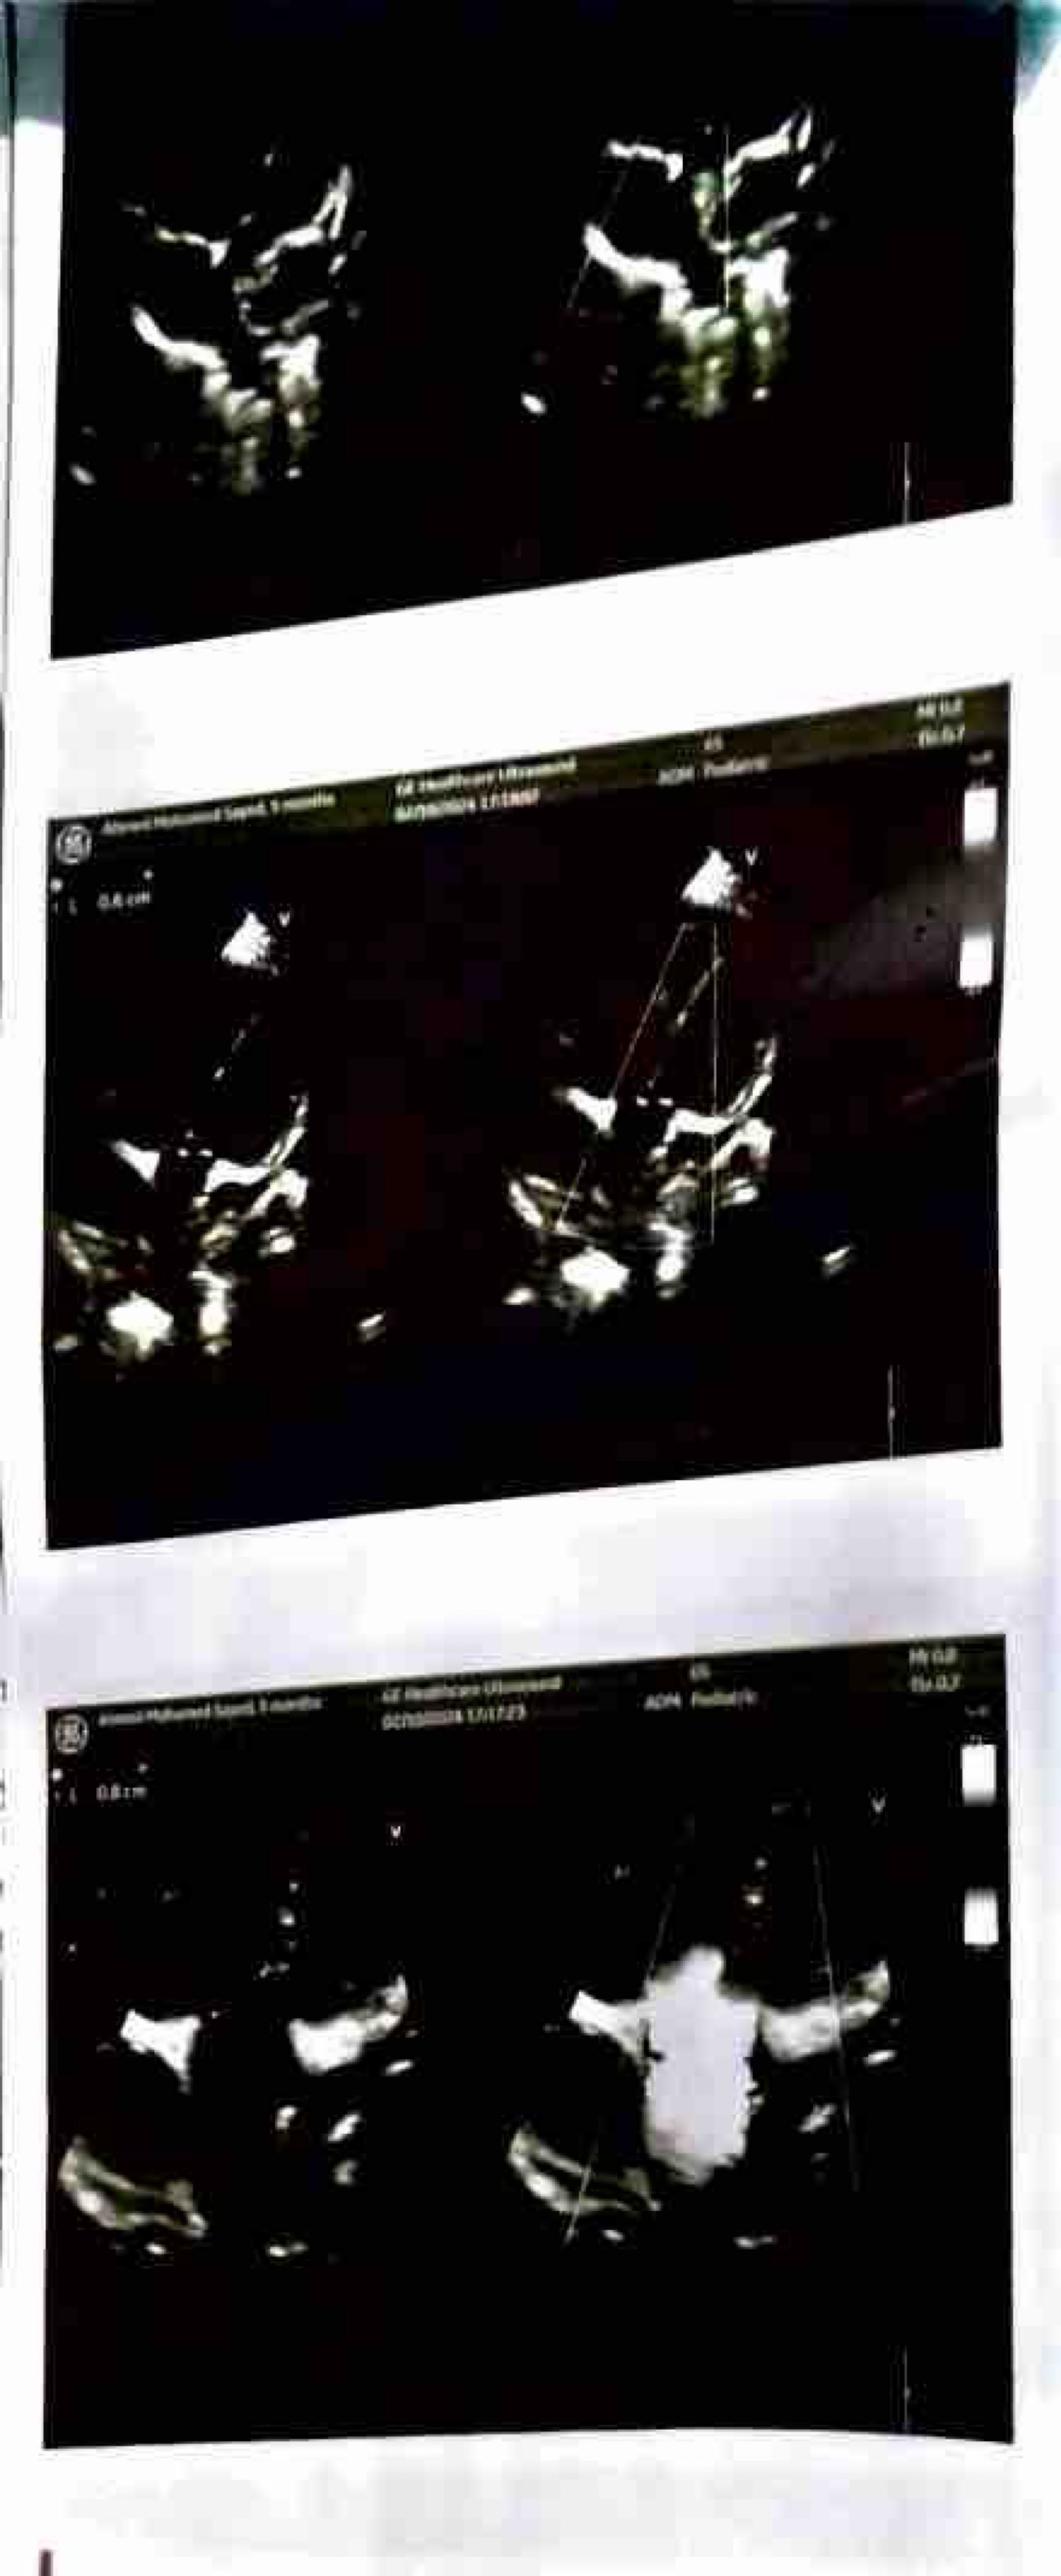

My name is Fahad and I’m looking to help my colleague who is fundraising for her friend in Egypt whose 15 month old child Ahmed is currently suffering from a heart abnormality.